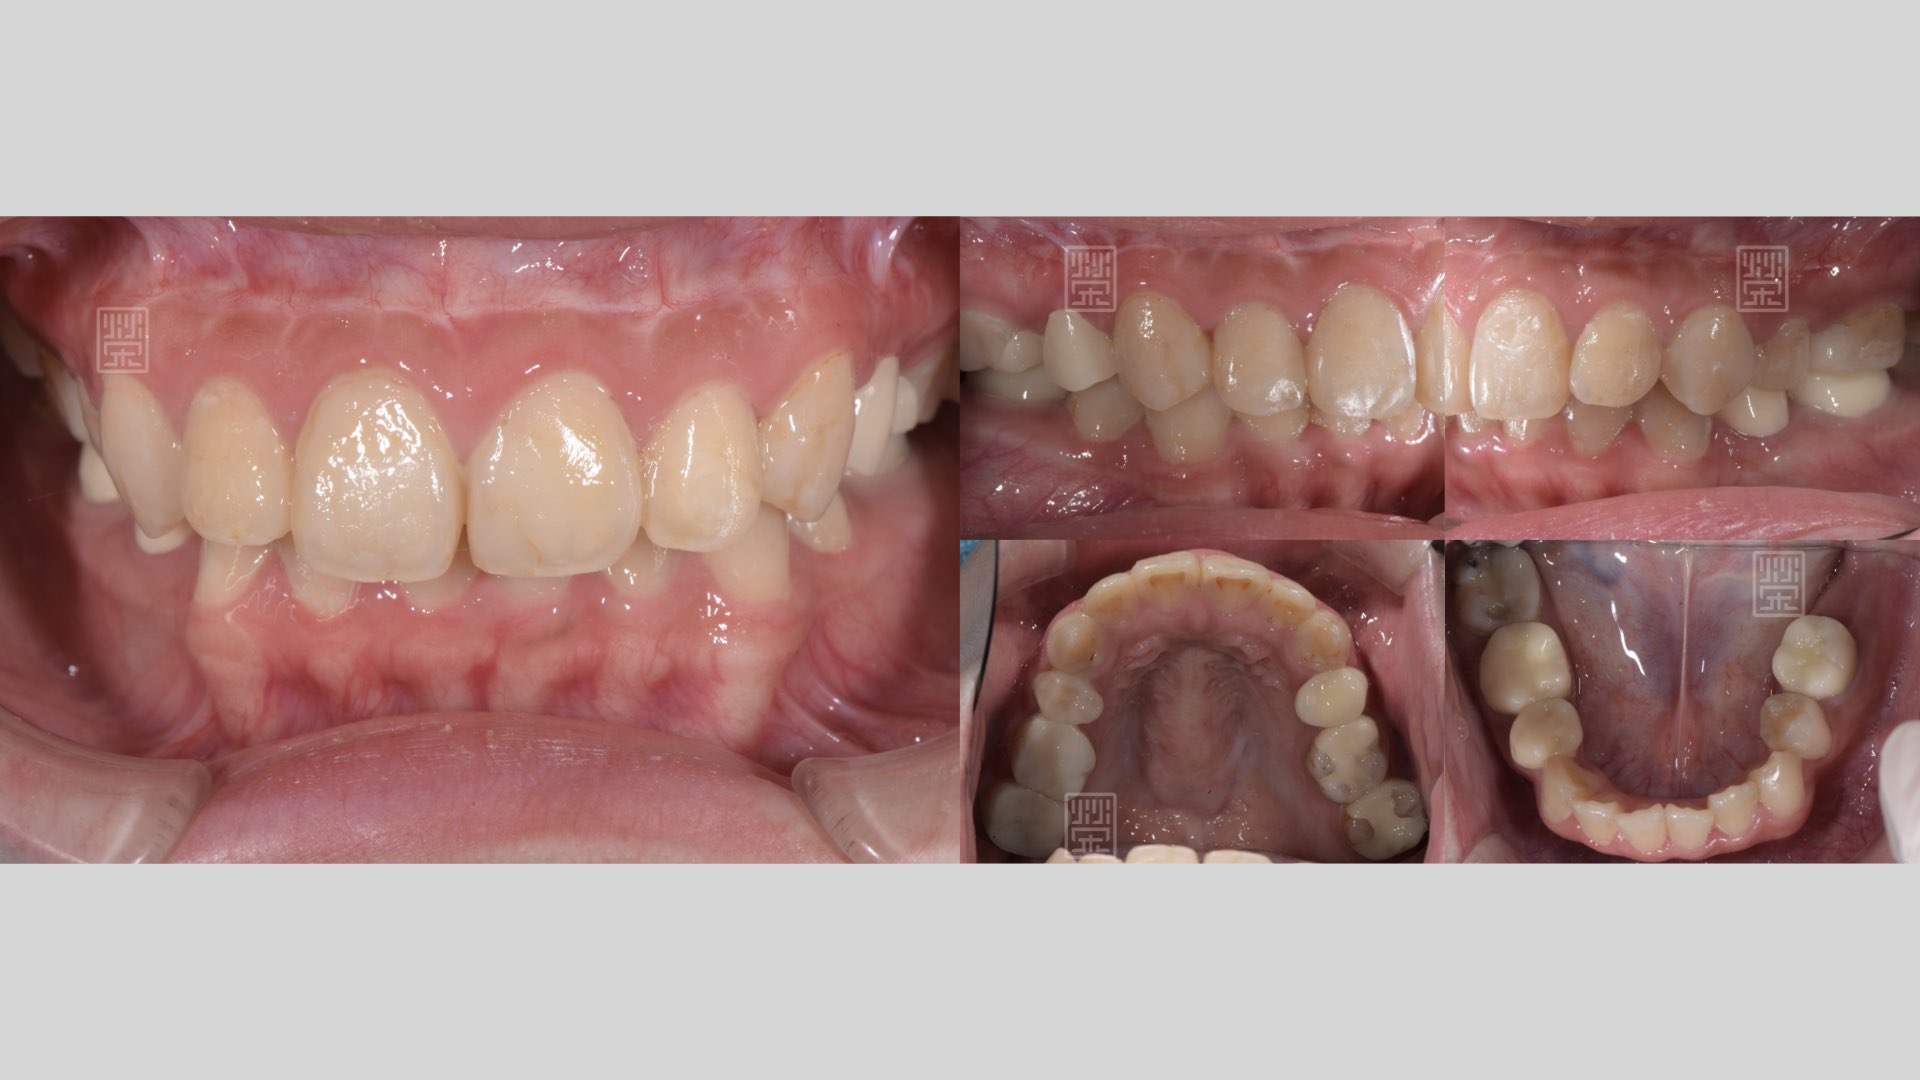

全瓷嵌體完成

全瓷貼片完成